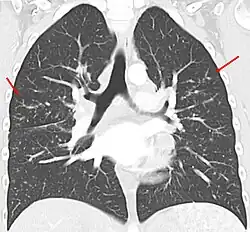

Sarkoidoza, choroba Besniera-Boecka-Schaumanna (łac. sarcoidosis) – choroba układu odpornościowego charakteryzująca się powstawaniem ziarniniaków (małych grudek zapalnych), które nie podlegają martwicy. Praktycznie każdy organ może być nią dotknięty, chociaż najczęściej pojawia się w węzłach chłonnych i płucach. Objawy mogą się pojawić nagle, ale najczęściej postępują stopniowo. W obrazie rentgenowskim płuc sarkoidoza może przypominać gruźlicę lub chłoniaka.

W obrębie układu oddechowego sarkoidoza najczęściej objawia się jako choroba restrykcyjna płuc powodująca spadek ich objętości oraz podatności (zdolności do rozciągania). Pojemność życiowa płuc jest zmniejszona i większa część powietrza może ulec wydmuchnięciu w ciągu pierwszej sekundy (wzrasta FEV1). To oznacza, że stosunek FEV1/FVC również wzrasta.